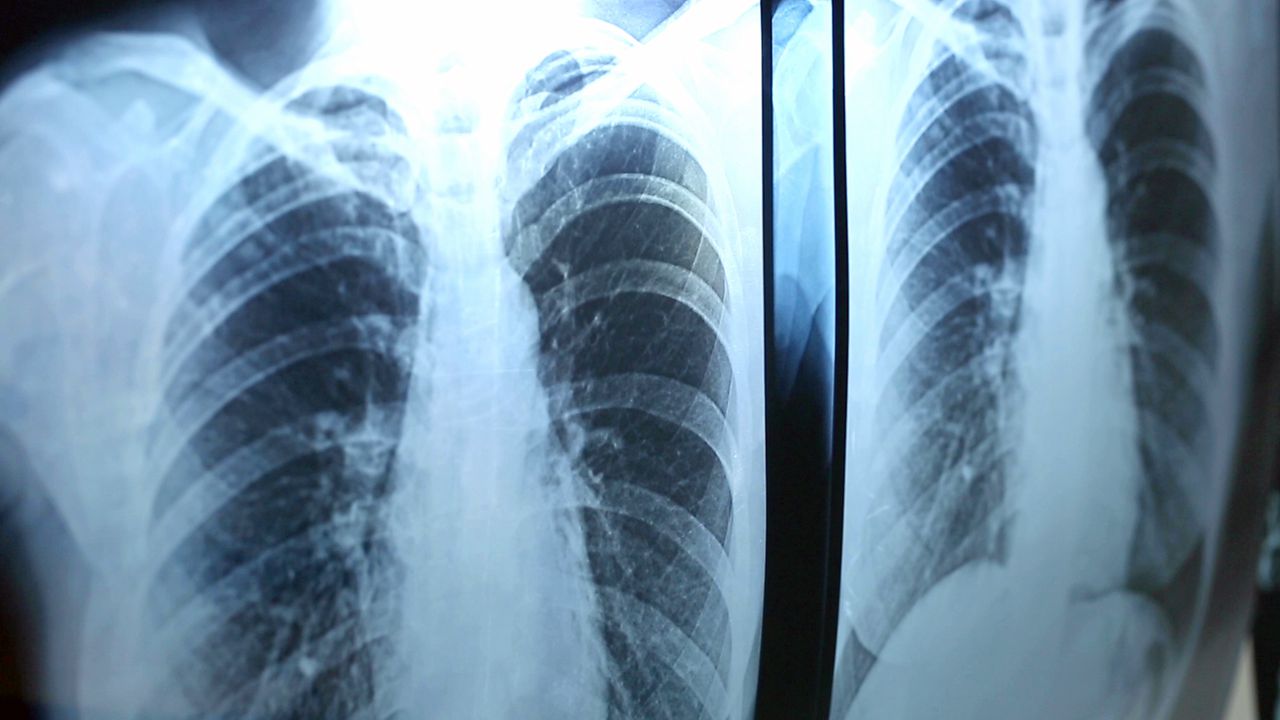

To find out what's wrong, your pulmonologist looks at a range of factors. They give you a physical exam. They study your health history. They may order different types of tests. For example, you may need to have a CT scan or a bronchoscopy. They may give you a spirometry test or a sleep study. Your pulmonologist uses all of this info to develop a care plan that's right for you.